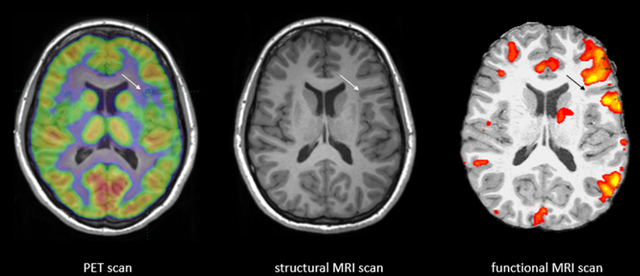

• MRI and fMRI

MRI and fMRI

Allows doctors to see what the brain looks like and what it does